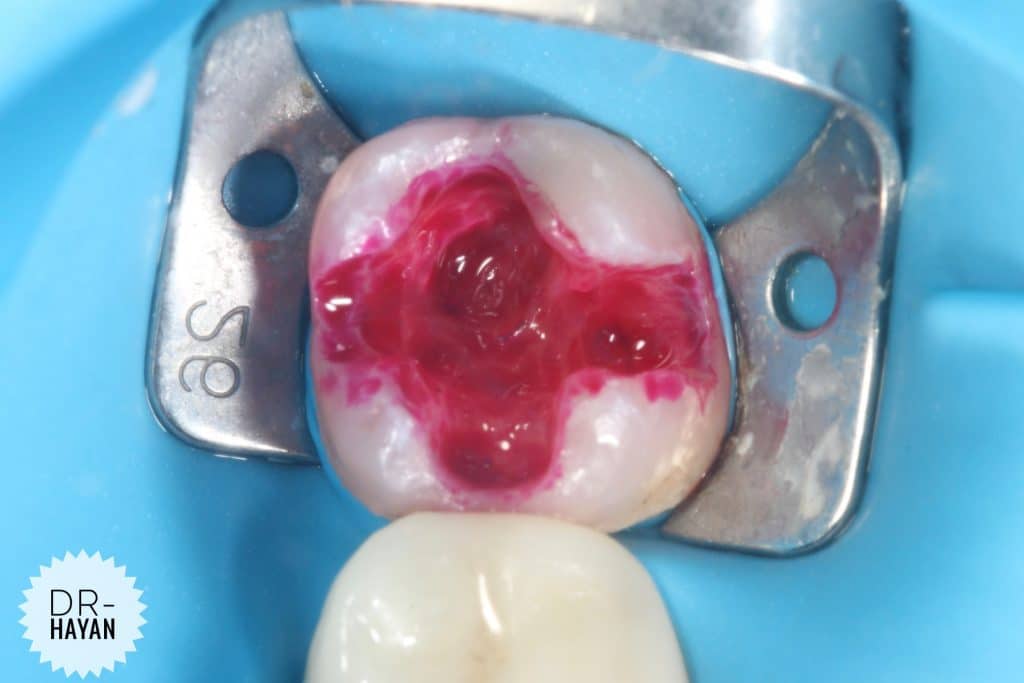

After remove the amalgam

As usual , recurrent caries under it

Remove the caries & finishing the margin

CDD

Although caries indicating dyes are not highly specific, the intensity of the stain can be utilized to selectively remove stained areas. In general, areas with a darker, more intense stain tend to have a greater degree of demineralization and carious bacteria. Areas with a lighter stain may not be affected and can be left in place.

Some infected dentine

you can note the different under magnification , specifically around the discoloration dentine